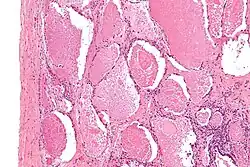

| Micrograph of pulmonary alveolar proteinosis, showing the characteristic airspace filling with focally dense globs referred to as chatter or dense bodies. H&E stain. | |

Lung washings or tissue for histopathologic analysis are most commonly obtained using bronchoalveolar lavage and/or lung biopsy.[13] Characteristic biopsy findings show filling of the alveoli (and sometimes terminal bronchioles) with an amorphous eosinophilic material, which stains strongly positive on PAS stain and the PAS diastase stain. The surrounding alveoli and pulmonary interstitium remain relatively normal.[14] Electron microscopy of the sample, although not typically performed due to impracticality, shows lamellated bodies representing surfactant.[15] An alternative diagnosis with similar histomorphologic findings is Pneumocystis jirovecii pneumonia.[15]

Lung washings characteristically yield a fluid which is "milky"composition. Under the microscope, samples show 20-50 micrometer PAS-positive globules on a background of finely granular or amorphous PAS-positive material. There is typically a low numbers of macrophages and inflammatory cells (although this is variable).[14][15]